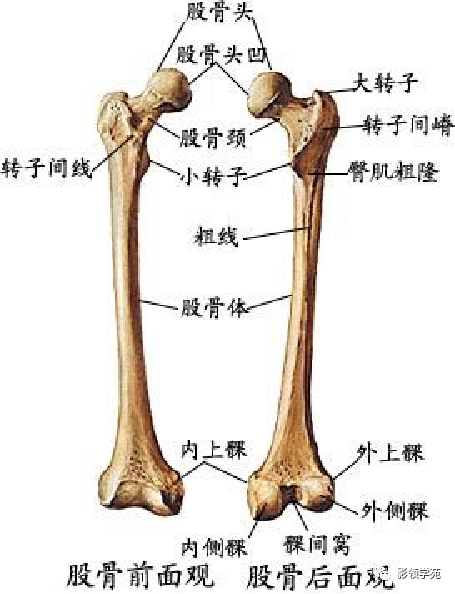

骨骼系统

骨骼系统